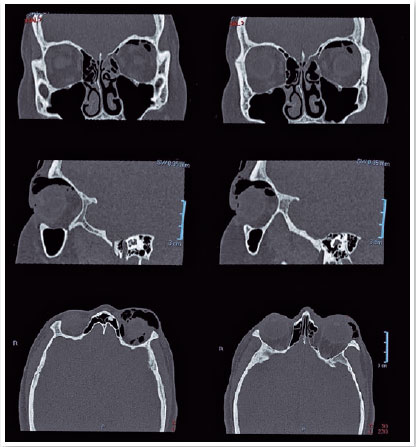

TC de Órbitas

O exame de órbitas requer cortes finos e reconstruções multiplanares para adequada avaliação das estruturas:

| Reconstruções | Axiais e coronais (2-3 mm) | Axiais, coronais e sagitais (1 mm) |

Orientações:

- Posicionar o paciente com o plano orbitomeatal paralelo à mesa

- Aquisição do ápice orbitário até o assoalho da órbita

- Reconstruções coronais oblíquas paralelas ao nervo óptico

- Para estudo de corpo estranho, usar algoritmo sem artefato de metal

- Em casos de trauma, avaliar sempre a integridade do canal óptico

TC de Órbitas com Reconstrução 3D

Técnica útil para avaliação de fraturas complexas e planejamento cirúrgico. Requer aquisição com cortes finos e reconstruções especiais.

Protocolo Recomendado:

- Aquisição isotrópica (0.5-0.6 mm)

- kV reduzido (100-110) para minimizar dose no cristalino

- Reconstruções em MPR (Multiplanar Reconstruction) e 3D

- Algoritmo de alta resolução para avaliação óssea